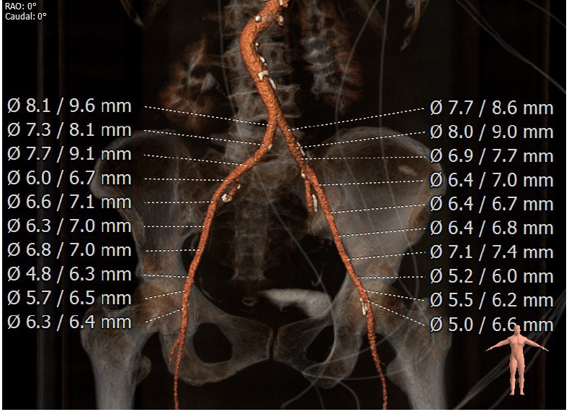

2、腹主动脉迂曲,升主动脉增宽;

CT分析:

根据测得的瓣环直径,结合患者二叶式主动脉瓣,瓣叶见钙化,以及畸形的有效开口,术中决定采用Evolut PRO 23mm瓣膜。递送系统顺利过弓跨瓣,球囊预扩后目标深度开始释放,得益于可回收设计,术中再回收进行一次位置调整,最终目标位完美释放,瓣膜立即工作,展开形态良好,无冠脉阻挡,无传导阻滞发生,术后压差<10mmHg,血流动力学稳定,手术圆满成功。